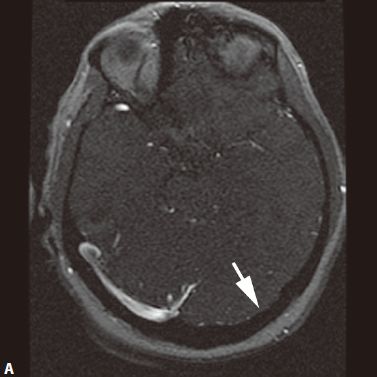

三、颅内动脉瘤

定义:颅内动脉局灶性异常扩大。

1. CT平扫为圆形高密度影,边缘清楚、增强有均匀强化,CTA或MRA可明确显示动脉瘤及其与载瘤动脉的关系。瘤样凸起。

2. 动脉瘤的瘤腔在T1WI、T2WI上均呈低信号,动脉瘤内有涡流时,也可产生轻微的不均质信号;瘤内血栓显示为高低相间的混杂信号。